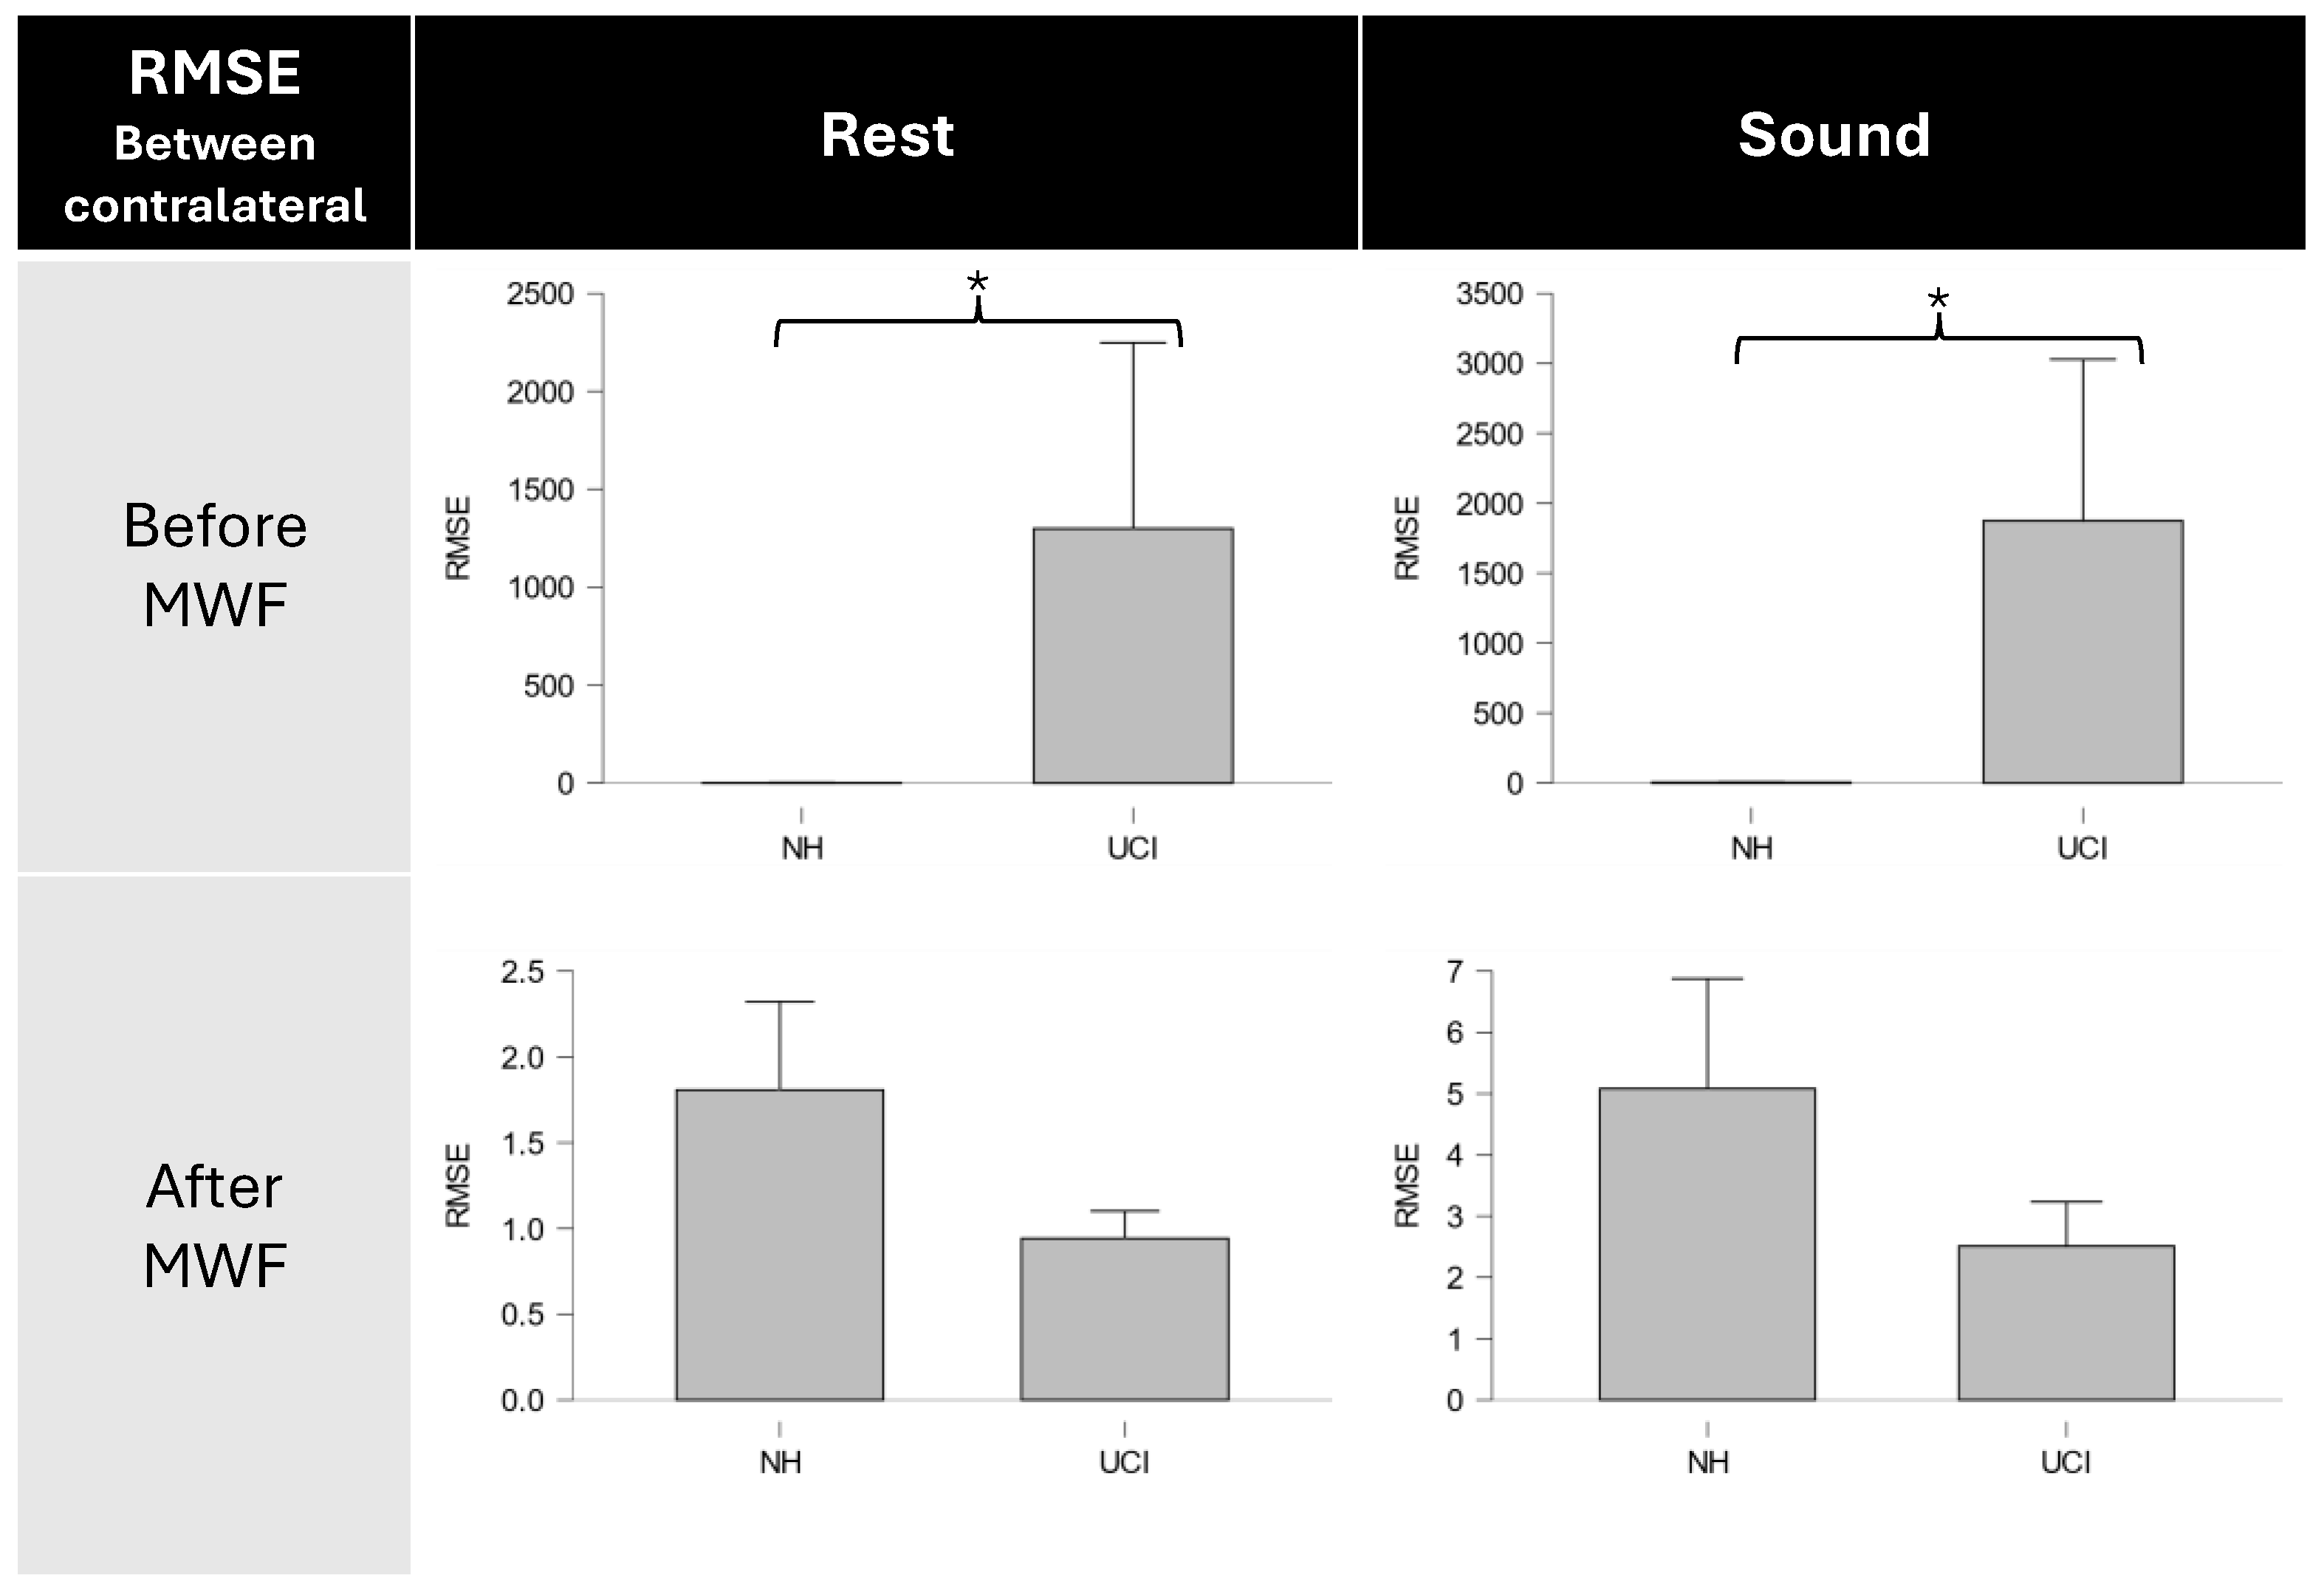

3.2. CI Artifact Reduction

3.3. Neurophysiological Results